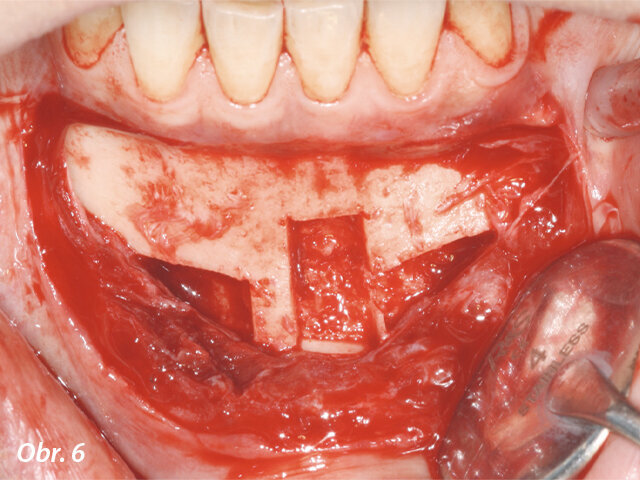

Do frontálního úseku horní a dolní čelisti bylo aplikováno anestetikum. V dolní čelisti byl z kortikální kosti odebrán vzorek a pomocí piezoelektrického zařízení proveden řez ve spongiózní kosti. Štěpy byly odebrány z bradové symfýzy, co nejblíže k dolnímu okraji mandibuly, aby nedošlo k narušení citlivé inervace řezáků, což bývá při tomto zákroku častou komplikací. Jizva ve vestibulární kortikální kosti byla perforována pomocí malého kulatého vrtáku, což umožnilo rychlou revaskularizaci štěpů. Poté byly štěpy umístěny na své místo a zajištěny šroubky (obr. 6, 7).

Kostní štěpy byly odebrány z bradové symfýzy a pevně zajištěny v místě transplantace chirurgickými šroubky.